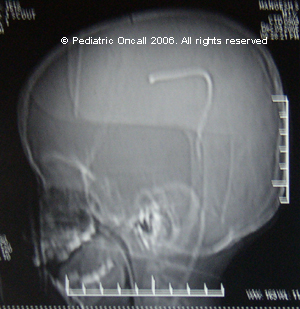

VP shunt

What is the diagnosis?

VP shunt. The most effective treatment of hydrocephalus is insertion of a shunt {at a known pressure gradient}. The shunt is a hollow silicone tube, placed into the ventricular system, diverting the CSF flow to the peritoneal cavity of the abdomen {VP shunt}. If abdominal cavity is unable to absorb the fluid due to some disease viz. TB or cyst, the shunt can be placed via the jugular vein to reach the right atrium of heart {VA shunt}. Shunts can also be placed in the pleural {chest} cavity.